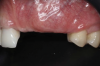

Fig 16. Final clinical outcome at 12 months post–iCTG augmentation.

Figure 16

After 3 months of healing, the second-stage procedure was performed to uncover the dental implants. Then, after 6 months of soft-tissue conditioning with temporary crowns, the case was completed with permanent, implant-supported restorations (Figure 16 and Figure 17).

One of the main endpoints of implant therapy in the anterior region is patient satisfaction, and this can be highly dependent on the level of the peri-implant soft-tissue margin and the height of the peri-implant papillae.7,8,19 The bone augmentation procedures provided an adequate bone volume and height that enabled the placement of the three dental implants in ideal prosthetically and biologically driven positions. These procedures, however, often result in displacement of the MGJ.5,15,17,18 The first soft-tissue augmentation surgery aimed at increasing soft-tissue thickness in a horizontal and vertical aspect.7,12,20 The iCTG augmentation technique involved augmentation of mucosal thickness on the buccal aspect, which has been demonstrated to have beneficial effects on marginal bone level stability over time,20,21 and augmentation of the interproximal soft tissue, which can result in higher and thicker peri-implant papillae.3,4,10,22 This augmentation procedure requires closure by primary intention to maximize the gain in supracrestal tissue height, and therefore the distortion of the MGJ cannot be corrected with this bilaminar approach. The second soft-tissue augmentation surgery involves an apically positioned flap in combination with two labial strip gingival grafts.5,18 The primary goal of this procedure was in this case to reposition the MGJ on the buccal aspect, increasing keratinized mucosa width at the implant sites.5,18